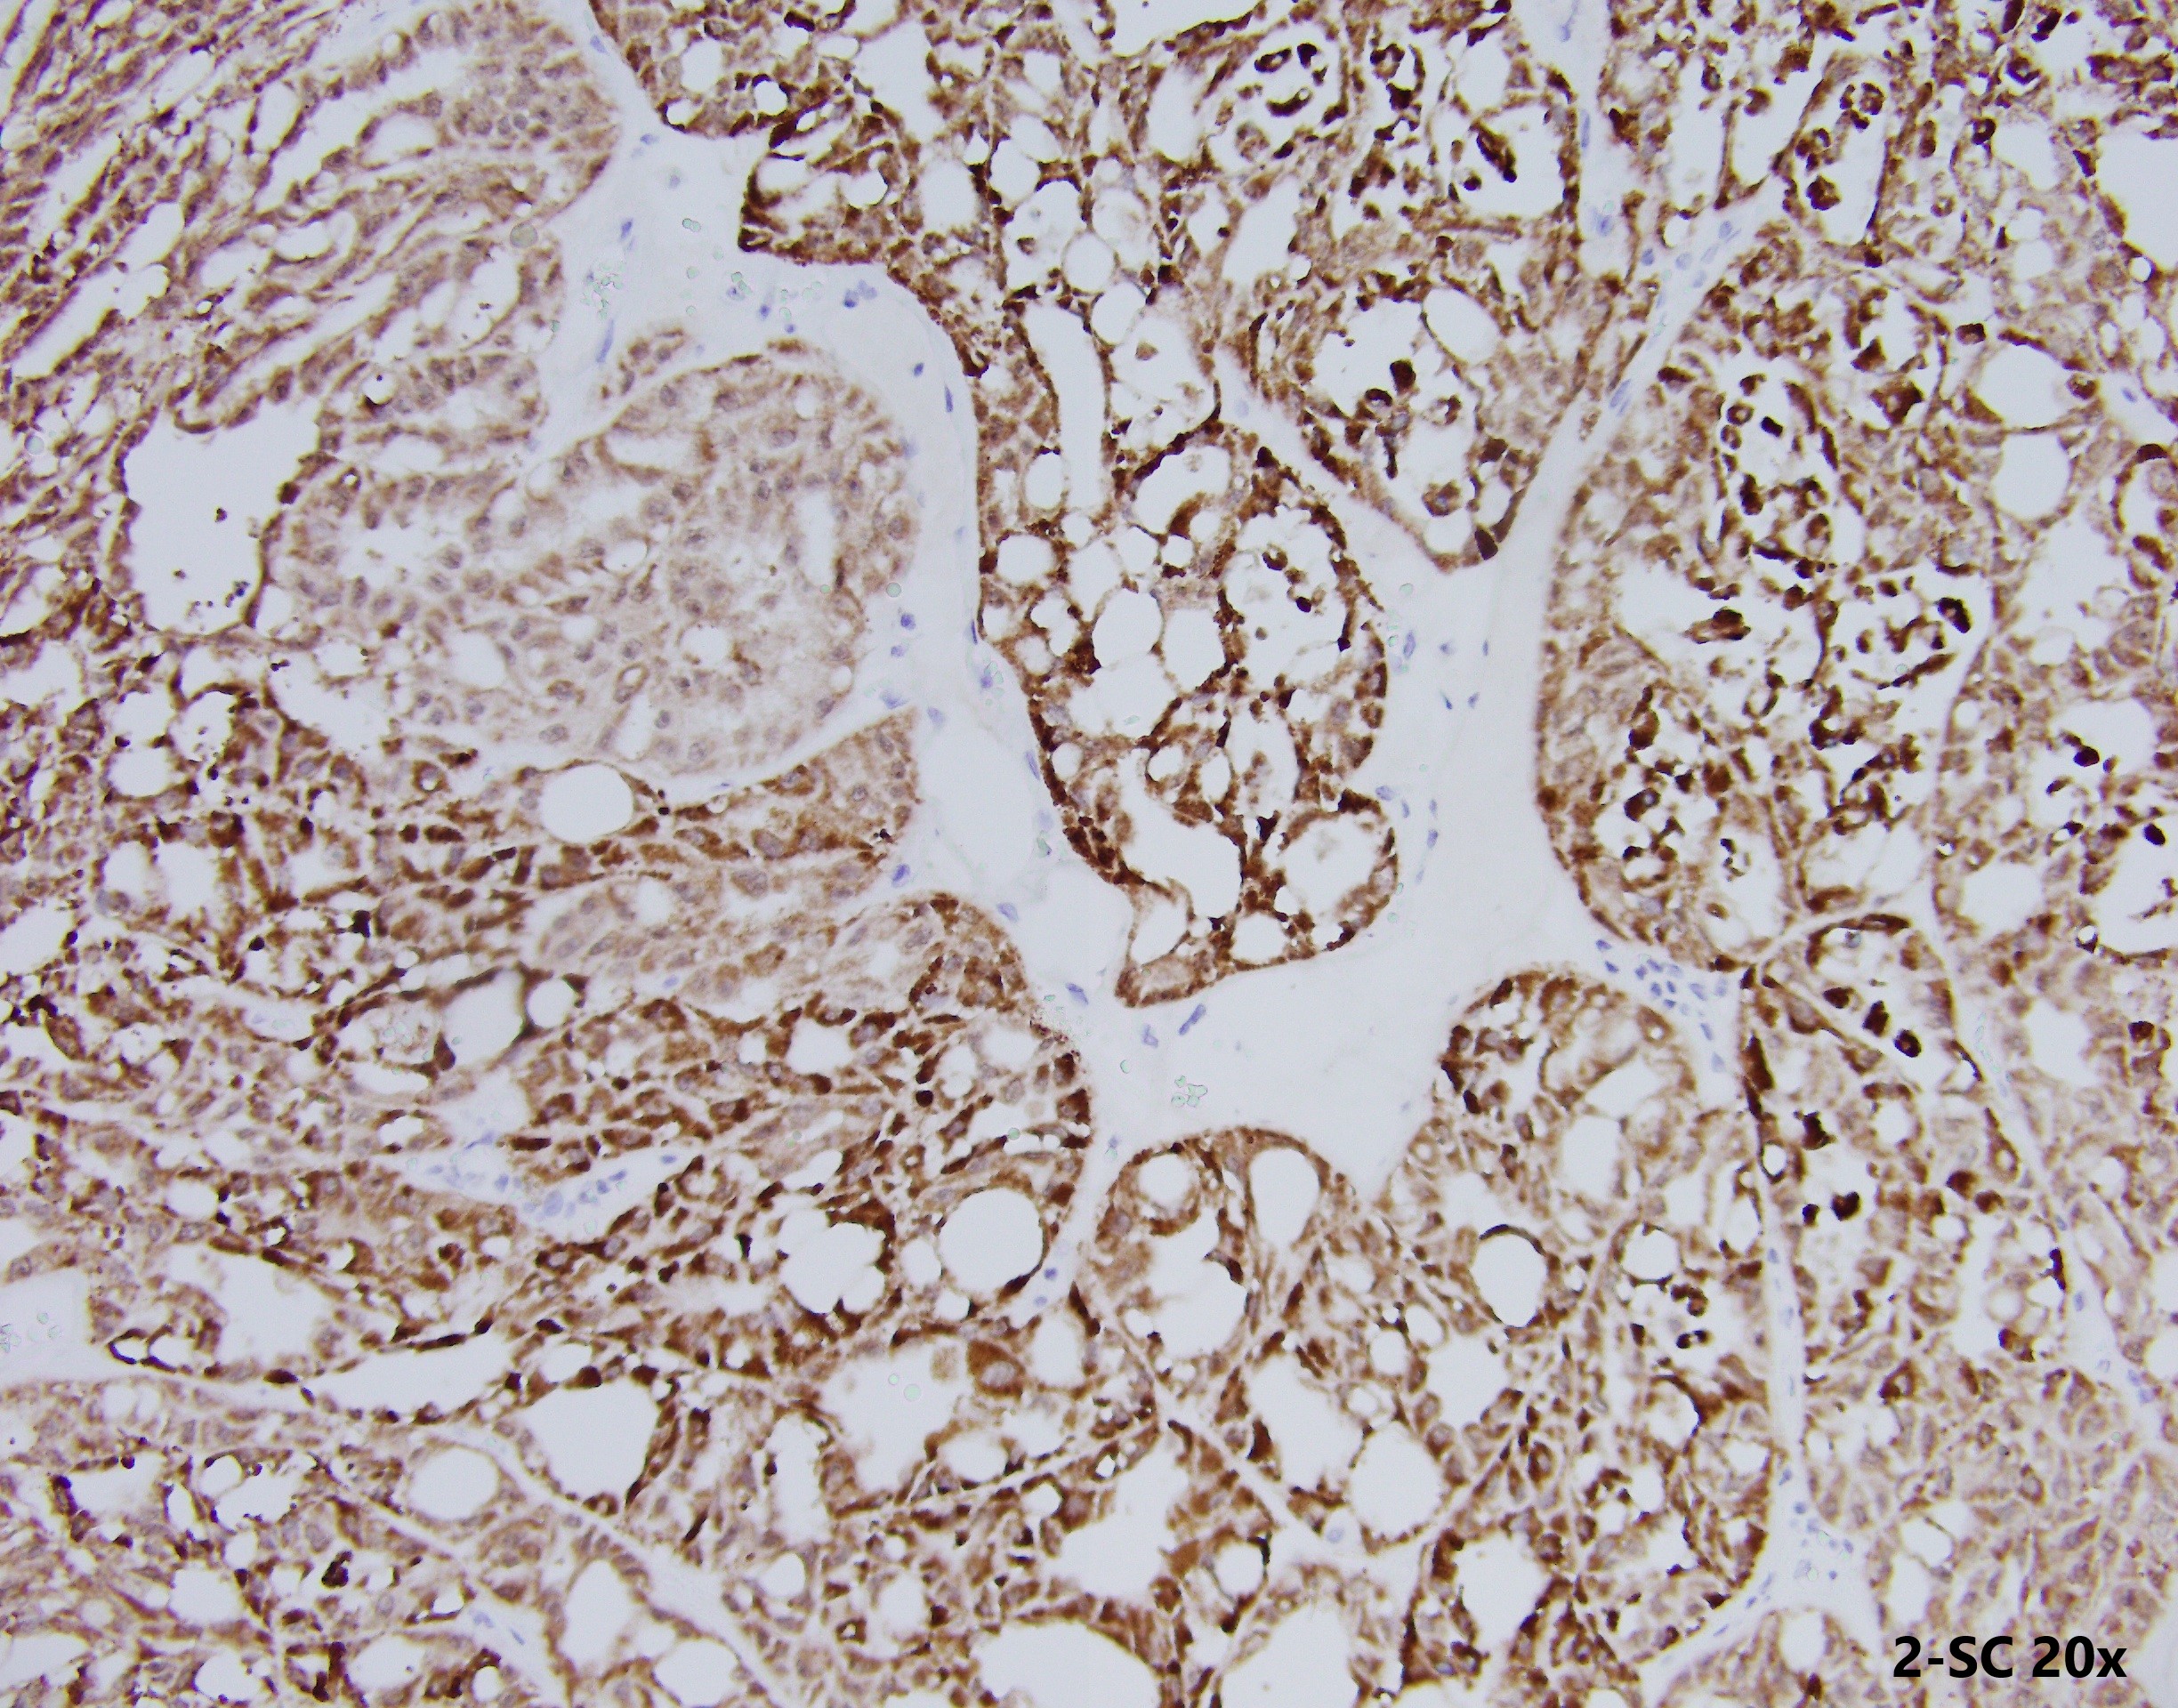

35 year-old-male with an 8 cm well-circumscribed, solid mass located in the upper pole of the left kidney with associated para-aortic metastasis. H&E, and IHC stains are shown.

Histologically, FH-deficient RCCs were originally described as type 2 papillary RCC and occasionally as collecting duct carcinoma (CDC), with a spectrum of architectural patterns including papillary, tubulopapillary, tubular, cribriform, solid and cystic elements. The morphological hallmarks of HLRCC are characteristic nuclear features: a large nucleus with a very prominent inclusion-like eosinophilic nucleolus surrounded by a perinucleolar halo. Based on these architectural and nuclear features, the differential diagnosis of HLRCC could include a variety of high-grade RCCs of different histological subtypes, particularly type 2 papillary RCC, CDC, or high-grade RCC, unclassified. Recently, an expanded histological spectrum of FH-deficient RCC has been described, including tubulocystic carcinoma with poorly differentiated foci, and SDH-deficient RCC like morphology was observed in FH-deficient RCC.

These tumours are characterised by negative immunohistochemistry for FH and aberrant succination of cellular proteins (2-succinylcysteine, 2SC). However, not all RCC show loss of FH stain by IHC (choice c is not right).